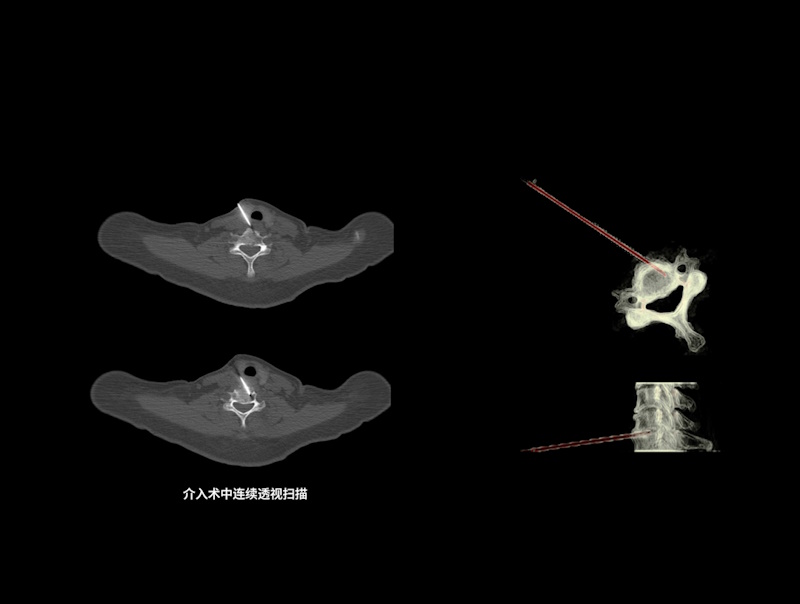

精准介入扫描方案

支持基于2D/3D进针路径精准规划,设置目标进针位置,自动计算进针路径长度和进针角度

支持单次断层扫描、单次螺旋扫描、连续断层扫描和连续透视扫描,以满足不同介入穿刺应用场景

KARL 3D双域迭代重建技术助力术后CT影像精准评估,在保证高清图像质量的同时有效降低扫描辐射剂量

提供完善专业介入套件,辅助医生床旁轻松完成病床控制、实时曝光扫描、图像浏览查看等操作